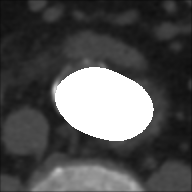

From ROIs are created the binary masks for each slice of the sequences both for basal and with CM.

Masks are produced with elliptical selection to include the entire vessel, and the pixels within the selected ellipse assumes as intensity value (white), while all the remaining ones takes (black).